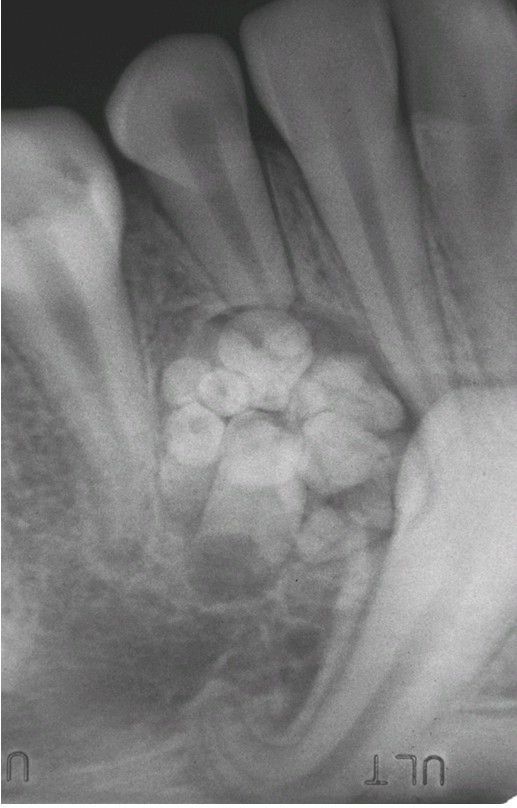

Dilaceration

Root angulation of a mandibular cuspid. Development has been altered by the presence of an adjacent compound odontoma